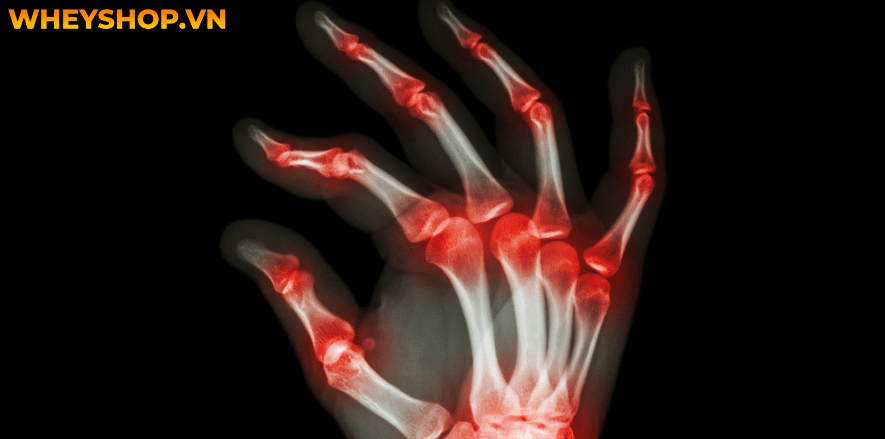

2.4 Viêm khớp ngón tay

Viêm xương khớp và viêm khớp dạng thấp thường là những loại khớp gây ra đau ở các đầu ngón tay, viêm khớp có thể ảnh hưởng đến các khớp ngón tay cái, giữa các ngón tay hoặc vùng gần móng tay. Triệu chứng bệnh có thể thấy được là ở giai đoạn đầu, bệnh viêm khớp gây ra cảm giác nóng rát ở các ngón tay, đặc biệt là các đầu ngón tay đau dù rất ít hoạt động.

Đau đầu ngón tay cảnh báo bệnh Viêm khớp ngón tay